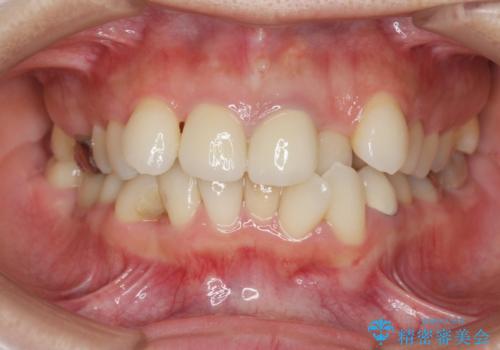

著しいがたつきによる清掃困難 歯牙抜去とセラミック治療

- 前歯の変色の改善を希望され来院されました。

X線写真より、充填剤の突き出た状態の根管治療の再治療を行い、セラミック治療を計画すると同時に、

歯ブラシがしづらく虫歯の原因となっている歯の位置の悪い右上側切歯の抜去を行います。

清掃を難しくしている歯を抜去することで虫歯の再発を防ぐような治療方針としました。